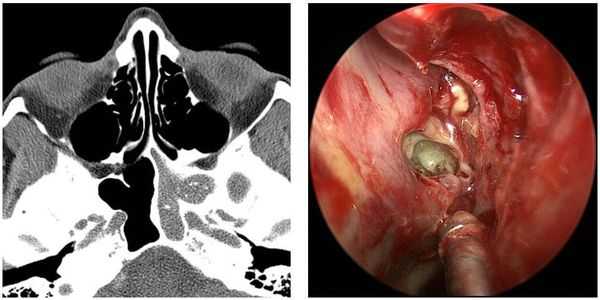

д) Грибковый синусит при эндоскопии. При эндоскопии возможно обнаружение двух форм грибкового синусита; инвазивного и неинвазивного. Инвазивный синусит, более знакомый врачам, хоть и нечастый, имеет три формы: молниеносную, хроническую и грануляционную. Мукоромикоз представляет собой молниеносный грибковый синусит, чаще всего им страдают пациенты с нарушением иммунитета. Он характеризуется деструкцией костных и мягких тканей, которые определяются на КТ и при эндоскопии; используются системные противогрибковые препараты и агрессивное хирургическое лечение.

Менее известны неинвазивные формы грибкового синусита: грибковое тело и аллергический грибковый синусит. Аллергический грибковый синусит характеризуется наличием полипов и слизеподобного содержимого зеленого цвета в пораженных пазухах, на КТ признаками являются костная деструкция той или иной степени и участки повышенной плотности в просвете затемненных пазух. В основе патогенеза аллергического грибкового синусита лежит ограниченный иммунный ответ на аллергены неинвазивных черных грибов (например, Bipolaris), его лечение заключается в удалении полипов и грибковых масс, обеспечении постоянной аэрации и очищения пазухи и, при необходимости, назначении кортикостероидов.